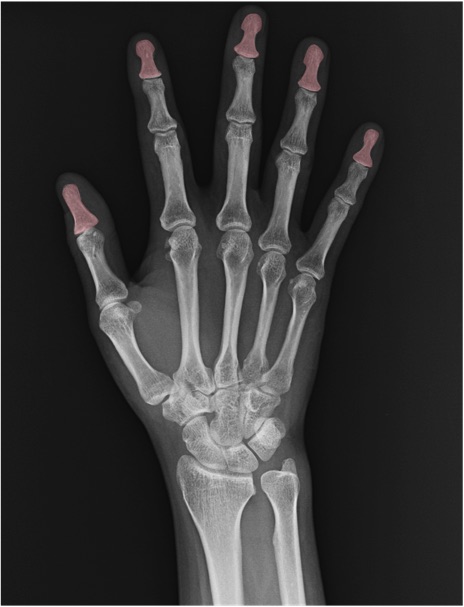

末節骨(distal phalanx)の手関節レントゲン画像における正常解剖

舟状骨(scaphoid)

月状骨(lunate)

三角骨(triquetrum)

中手骨(metacarpal bone)

基節骨(proximal phalanx)

中節骨(middle phalanx)

橈骨(radius)

尺骨(ulna)

尺骨茎状突起(ulnar styloid process)

CM関節(carpometacarpal joint)

IP関節(interphalangeal joint)

MP関節(metacarpophalangeal joint)

PIP関節(proximal interphalangeal joint)

DIP関節(distal interphalangeal joint)